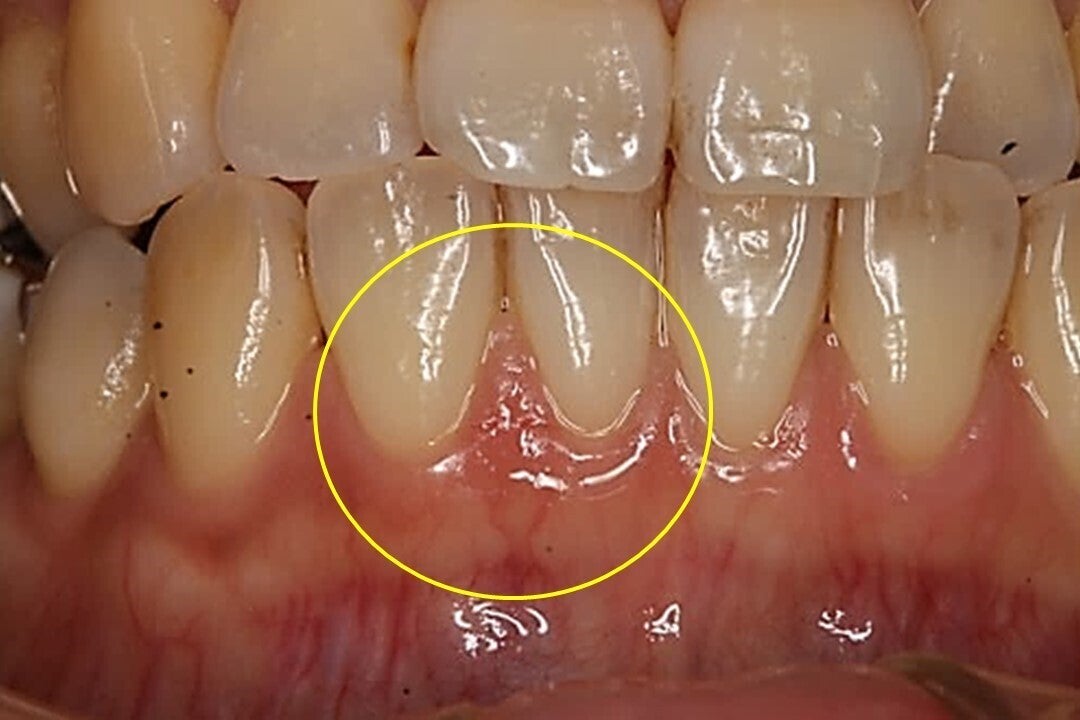

歯ブラシが原因と思われる傷

自分では見えない部分 やり過ぎになってしまう

開業以来、日々の診療の中で、磨き過ぎが原因と考えられる方が多数、来院されます。虫歯も無い、歯周病も無い、しかし、違和感や症状を訴える方がたくさんいらっしゃいます。

よく観察すると、歯ぐきに小さな傷があり、磨き過ぎが原因ではないかと考えました。それから辛抱強く歯みがき指導を行っていくと、大きな処置をしなくても、症状が軽減される方が増えていきました。

すべての方ではありませんが、小さな感触だったようなものが積み重なって、確信になり、指導を中心とした予防処置を行うようになりました。